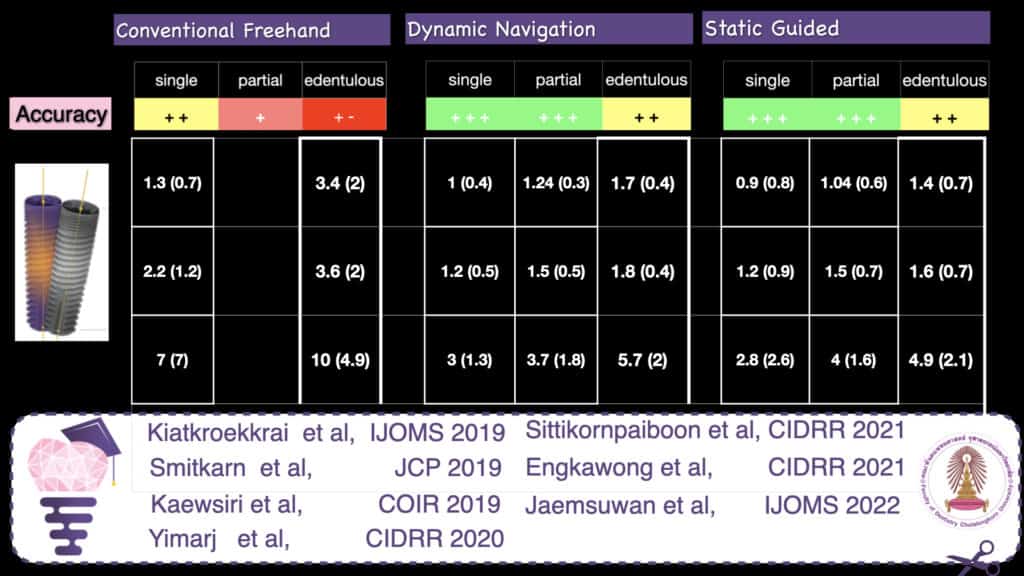

Accurate implant placement was the primary and most important advantage reported for CAIS. To measure the extent of this accuracy, researchers have used the 3-dimensional deviation from the planned position at the implant platform and apex and the deviation in the angle (Figure 1). Initial research pointed out to a significant increase in accuracy when CAIS was used, with the deviation reduced to roughly half of what it was in freehand implant placement for single implants. An earlier systematic review from the ITI Consensus Workshop of 2017, found that static CAIS would result to deviation of 1.2 mm at implant platform on average (1), suggesting that a safety margin of 2mm is to be considered when we use this technology. Although certainly a great development, is this something that could transform your practice? Many colleagues remained skeptical, especially those with long experience. After all, gadgets are always cool, but we’ve been placing implants with great success already. Is it worth all additional investment and effort?

Accuracy of CAIS systems

Back the main point now: how accurate is implant placement when we use CAIS? To answer this allow me to discuss the results we have accumulated through a major CAIS research project in our clinic at Chulalongkorn University in the past 3 years (3,6-11). This project has by now involved more than 200 patients and included research protocols in many different clinical scenaria. The strength of this project is that it allows us to shape a comprehensive view of the effectiveness of CAIS, while limiting as much as possible the variation of the workflow error. A typical systematic review will compile numbers from many published studies, e.g. 2 studies from centre A on single gaps and 1 study from centres B and C each on fully edentulous patients. It would be very difficult to draw any valid conclusions on the accuracy of CAIS in single gaps as opposed to fully edentulous, because the 3 studies essentially report the results of 3 different workflows. The three centres use a different CBCT machine, a different planning software and in the case of static CAIS they might be using different printers and guided surgery implant systems. With all these different parametres contributing differently to the potential errors, it is impossible to conclude what is the impact of the clinical condition (single gap vs fully edentulous) in the finally reported accuracy numbers.

By standardizing the studies however and using the same technology and software, the same operators , clinic set up, as well as the same patient pool like we have done in this project, we can at least ensure that the workflow error is similar in all cases thus the observed differences can be attributed to the clinical conditions we investigate.

And at last, time to talk some numbers, which you can see in Figure 6. The table is compiled out of a series of published studies in our centre, where all cases were treated by the same team, using the same CBCT machine as well as planning software and implant system. Streamlining the workflow, one can now see a clear trend with the accuracy of CAIS being closer to freehand at single gaps, while the deviation drastically increases as we move to partially and fully edentulous patients. The deviation also trends to be slightly higher in dynamic than static guided when we are dealing with partially and fully edentulous cases, but at the same time both static and dynamic CAIS perform increasingly (and significantly) better than freehand placement, as complexity increases.